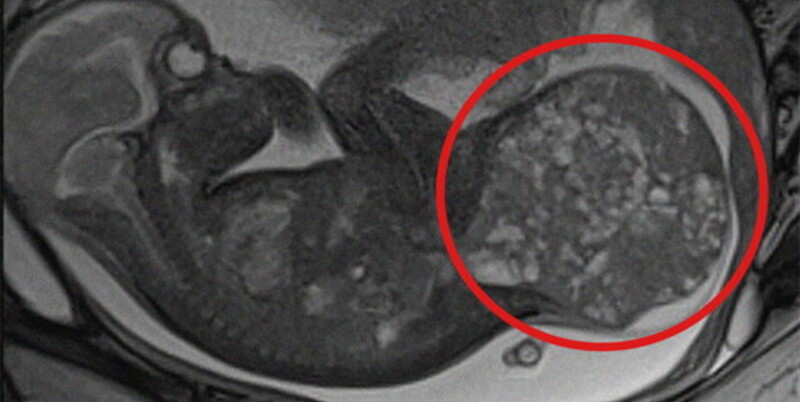

A daganat, amelyet szakrokokcigeális teratómának nevezik, ritka – többnyire jóindulatú – kinövés, amely a gerinc alsó részén, a keresztcsont (farokcsont) tájékán fejlődik ki.

Ebben az esetben a daganat gyorsan növekedett, ami komoly szövődményeket okozhatott volna a magzat számára, ezért az orvosok úgy döntöttek, hogy két összetett műtéti beavatkozást végeznek – számolt be róla az Ansa hírügynökség.

A kórház közlése szerint az első beavatkozást – egy méhen belüli műtétet – a terhesség 28. hetében hajtották végre a San Pietro kórházban, a Bambino Gesù klinika orvoscsoportjának közreműködésével. A sebészek lézeres koagulációval lezárták azokat az ereket, amelyek a daganatot táplálták, hogy lelassítsák annak növekedését.

A második beavatkozásra közvetlenül a szülés – császármetszés útján – után került sor, amikor a baba mindössze 1,9 kilogramm volt. A mintegy 800 grammos daganatot egy háromórás műtét során sikeresen eltávolították, és egyúttal rekonstruálták a keresztcsonti régiót is.